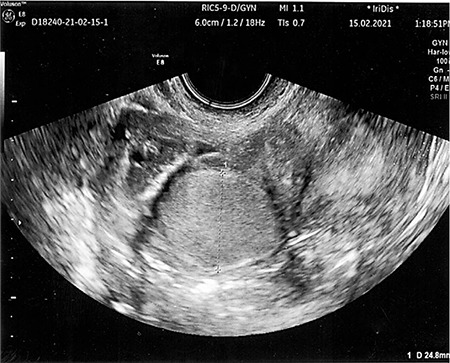

Hemangioma in female reproductive organs, particularly in the fallopian tube (FT), is a sporadic disease. In this report, we describe a case of hidden capillary hemangioma in FT in a 39-year-old woman who suffered from uterine leiomyoma. During the preoperative stage, pelvic sonography, computed tomography, and diagnostic laparoscopy revealed a subserous leiomyomatous nodule located along the posterior wall of the uterus. Despite this, intraoperatively, a benign vascular neoplasm was diagnosed. Histologically, it is characterized by multiple thin-walled vascular spaces lined with a single layer of endothelial cells, in which single mitoses were observed. The diagnosis was then confirmed immunohistochemically by CD31 and CD34 expression in the endothelial cells lining the inner surface of the spaces and the low mitotic activity of the tumor cells. It is virtually impossible to diagnose this asymptomatic neoplasm before and during surgery, which can result in an inadequate number of surgeries. Incorrect interpretation of a benign tumor at a young age can lead to unnecessary radical surgery with a resulting loss of fertility, and an unrevealed malignant process can threaten life.